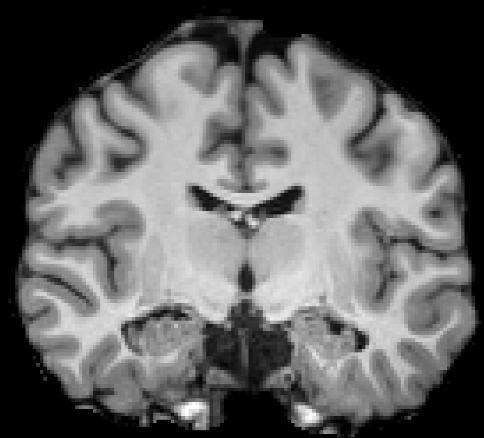

Let be a collection of -w images with a corresponding expert manually labeled image set . The paired collection is referred to as the training image set. Let be acquired with a pulse sequence , where is typically MPRAGE that presents a good gray-white matter contrast. For PSACNN, we require that in addition to , we have ; the corresponding NMR parameter maps for each of the training subjects. For each we have , where is a map of proton densities, and and store the longitudinal (), and transverse () relaxation time maps respectively. Most training sets do not acquire or generate the NMR maps. In case they are not available, we outline an image synthesis procedure in Section 2.5 to generate these from available -w MPRAGE images . Example images from are shown in Fig. 3.

We extract patches of size from voxels x of . is paired with a corresponding patch extracted from the label image . Training pairs of constitute the unaugmented data used in training. A CNN trained on only available unaugmented patches will learn to segment images with the exact same contrast as the training MPRAGE images and will not generalize to test images of a different contrast. We use the approximate forward models of pulse sequences as described in Section 2.2 to generate synthetic images that appear to have been imaged by that pulse sequence.